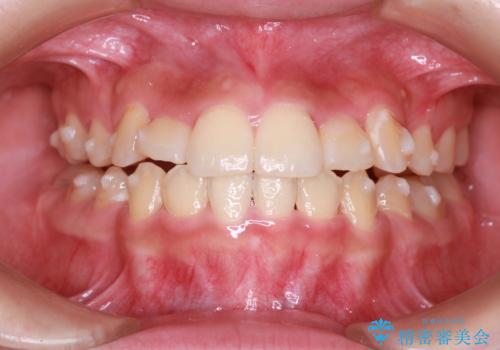

- 上下の前歯に激しい段差がある**重度の叢生(がたつき)**を主訴にご来院されました。精密検査の結果、歯をきれいに並べるためのスペースが圧倒的に不足していたため、上下左右の4番目の歯(第一小臼歯)を計4本抜歯する計画を立案しました。

本症例では、まず抜歯した大きなスペースを効率よく使い、歯の根元から大きく動かす必要があるため、初期段階にワイヤー矯正を採用。その後、細かな噛み合わせの調整や仕上げにインビザラインを使用する「ハイブリッドな矯正治療」で、期間の短縮と精度の高い仕上がりを目指しました。

治療の結果、重度のがたつきは跡形もなく解消され、抜歯したスペースもきれいに閉じました。ワイヤーによる「確実な移動」と、インビザラインによる「緻密な仕上げ」を組み合わせることで、審美性と機能性の両立を叶えた美しい歯並びを実現しました。